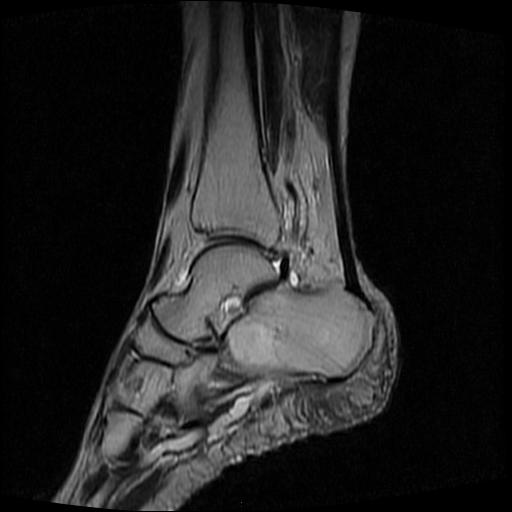

女性,70岁,右侧跟骨疼痛2个月,负重时加剧,不负重时不疼。

胫骨下段,跟骨、距骨可见斑片状异常信号区;考虑:转移瘤

跟骨cr片正常。

跟骨长t1长t2信号异常,边缘模糊(肿瘤一般边界清楚,故肿瘤不考虑),压脂像呈高信号--骨髓水肿(炎症?)。